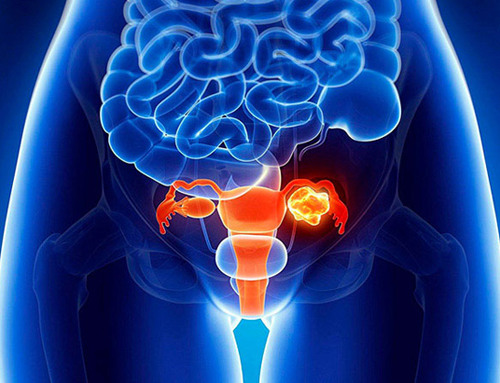

Dr. Mashru has completed his MBBS, MS in General Surgery and DrNB in Surgical Oncology, along with prestigious fellowships such as FIAGES and FALS (Oncology). His training includes extensive exposure to GI oncology, breast cancer surgery, thoracic oncology, urological cancers, head and neck cancers and gynecological oncology, with hands-on experience in both conventional and advanced surgical techniques.